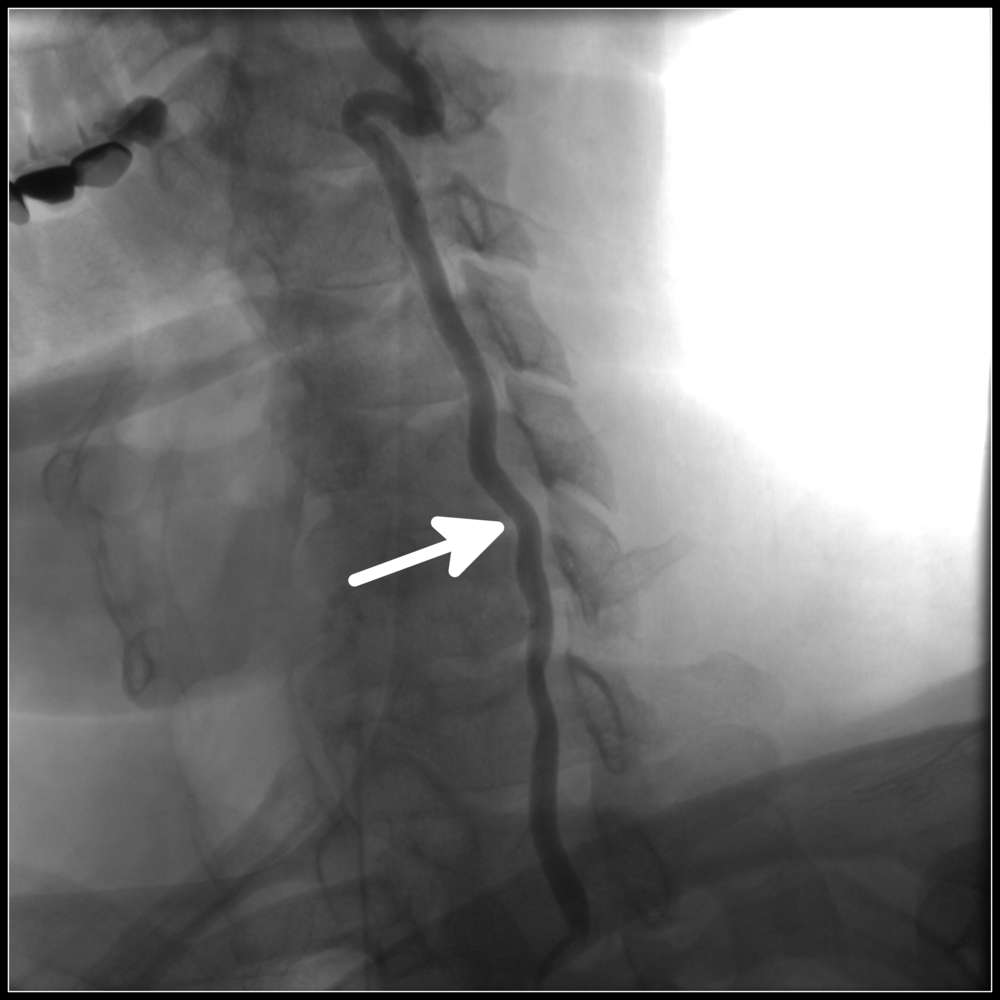

Позвоночная артерия представляет собой парное образование, берущее свое начало от подключичной артерии, которая в свою очередь отходит слева – от аорты, а справа – от плечеголовного ствола. Позвоночная артерия идет кверху и чуть назад, проходя позади общей сонной артерии, вступает в отверстие поперечного отростка шестого шейного позвонка, поднимается вертикально через аналогичные отверстия всех вышележащих позвонков, через большое затылочное отверстие вступает в полость черепа и следует к мозгу, снабжая кровью задние отделы мозга: мозжечок, гипоталамус, мозолистое тело, средний мозг, частично – височную, теменную, затылочную доли, а также твердую мозговую оболочку задней черепной ямки. До вступления в полость черепа от позвоночной артерии отходят ветви, несущие кровь к спинному мозгу и его оболочкам. Следовательно, при нарушении кровотока в позвоночной артерии возникают симптомы, свидетельствующие о гипоксии (кислородном голодании) участков мозга, которые она питает.

- Врожденные особенности строения артерии: патологическая извитость, аномалии хода, перегибы.

- Заболевания, в результате которых уменьшается просвет артерии: атеросклероз, всевозможные артерииты (воспаления стенок артерий), тромбозы и эмболии.

- Сдавления артерии извне: остеохондроз шейного отдела позвоночника, аномалии строения костей, травмы, сколиоз (это вертеброгенные, то есть связанные с позвоночником, причины), а также опухоли тканей шеи, их рубцовые изменения, спазм мышц шеи (это невертеброгенные причины).

Стоит отметить, что чаще развивается СПА слева, что объясняется анатомическими особенностями левой позвоночной артерии: она отходит от дуги аорты, в которой нередко имеются атеросклеротические изменения. Второй ведущей причиной, наряду с атеросклерозом, являются дегенеративно-дистрофические заболевания, то есть остеохондроз. Костный канал, в котором проходит артерия, достаточно узок, и при этом подвижен. Если в области поперечных позвонков имеются остеофиты, они сдавливают сосуд, нарушая приток крови к мозгу.

- дуплексное сканирование позвоночных артерий;

- вертебральную допплерографию с функциональными нагрузками (сгибанием/разгибанием/поворотами головы).